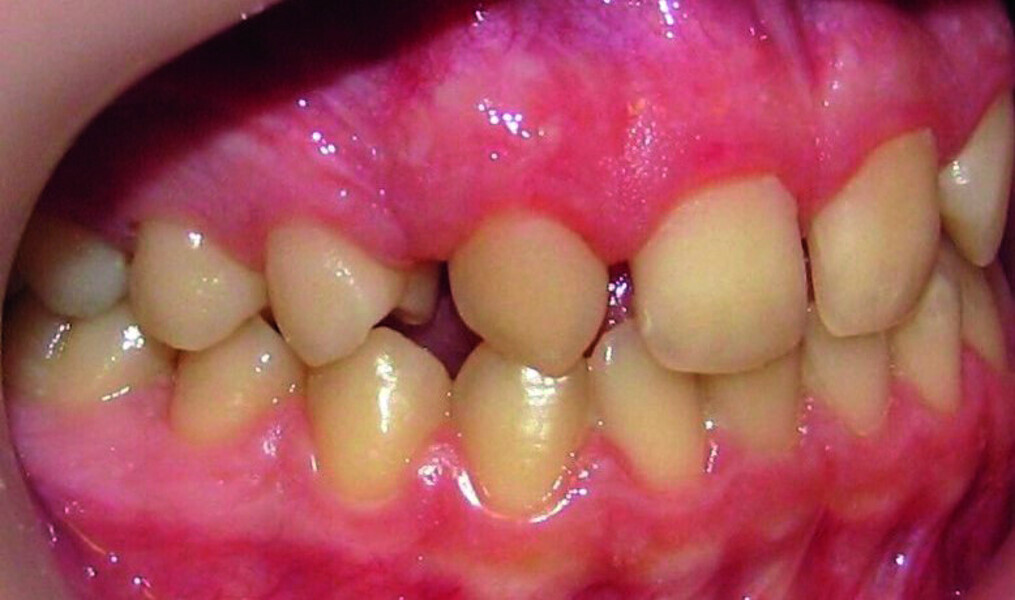

Orthodontic management of maxillary lateral incisors agenesis